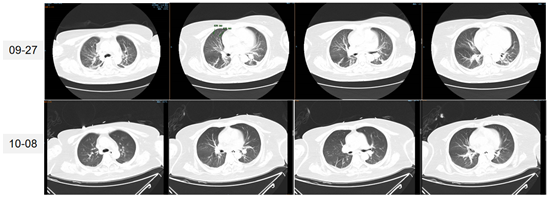

(2)抗感染(9月28日-10月15日):住院期间多次调整抗生素,使用了头孢他啶阿维巴坦、替加环素、多黏菌素B,但体温控制不理想。BALF培养出敏感肺炎克雷伯菌+耐药鲍曼不动杆菌,之后仅培养出耐药鲍曼不动杆菌,没有肺炎克雷伯菌。

图片

经过10余天左右的治疗,患者肺部感染明显控制和改善,但患者体温控制仍不理想,经常有超过39℃的高热。